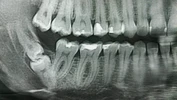

ألم الأسنان

تسوس الأسنان

نقص الأسنان

أمراض الأسنان واللثة

كيسات الفك

علاج الزرع